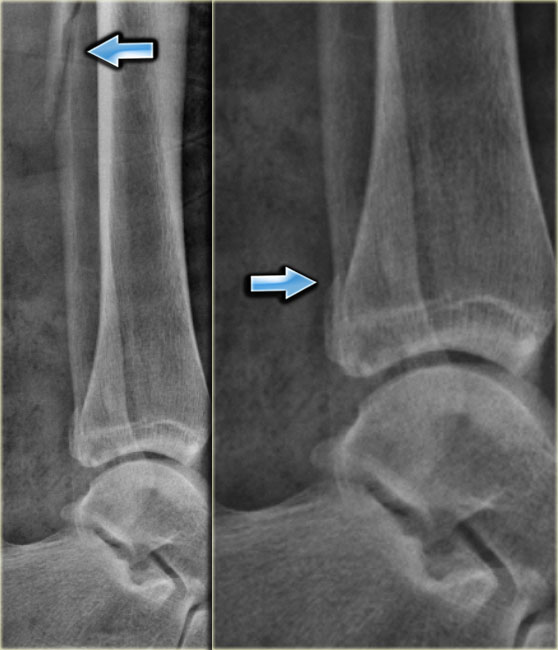

PE stage 1 PE stage 1

• Re-examination

On the ankle films there was no sign of an oblique fracture of the lateral malleolus, so we can exclude a Weber B fracture.

There is still the possibility of a Weber C fracture stage 4, i.e. medial rupture or avulsion, high fibular fracture and finally a posterior malleolus fracture.

At reexamination you notice the subtle avulsion of the medial malleolus (red arrow), which is stage 1.

Notice also the soft tissue swelling on the medial side (blue arrow)

PE stage 3 PE stage 3

Additional radiographs of the lower extremity were ordered and they demonstrate a high fibular fracture, i.e. Weber C stage 3 also known as a Maisonneuve fracture.

• Final report

Weber C fracture stage 4.

This is un unstable ankle injury that needs surgical repair.